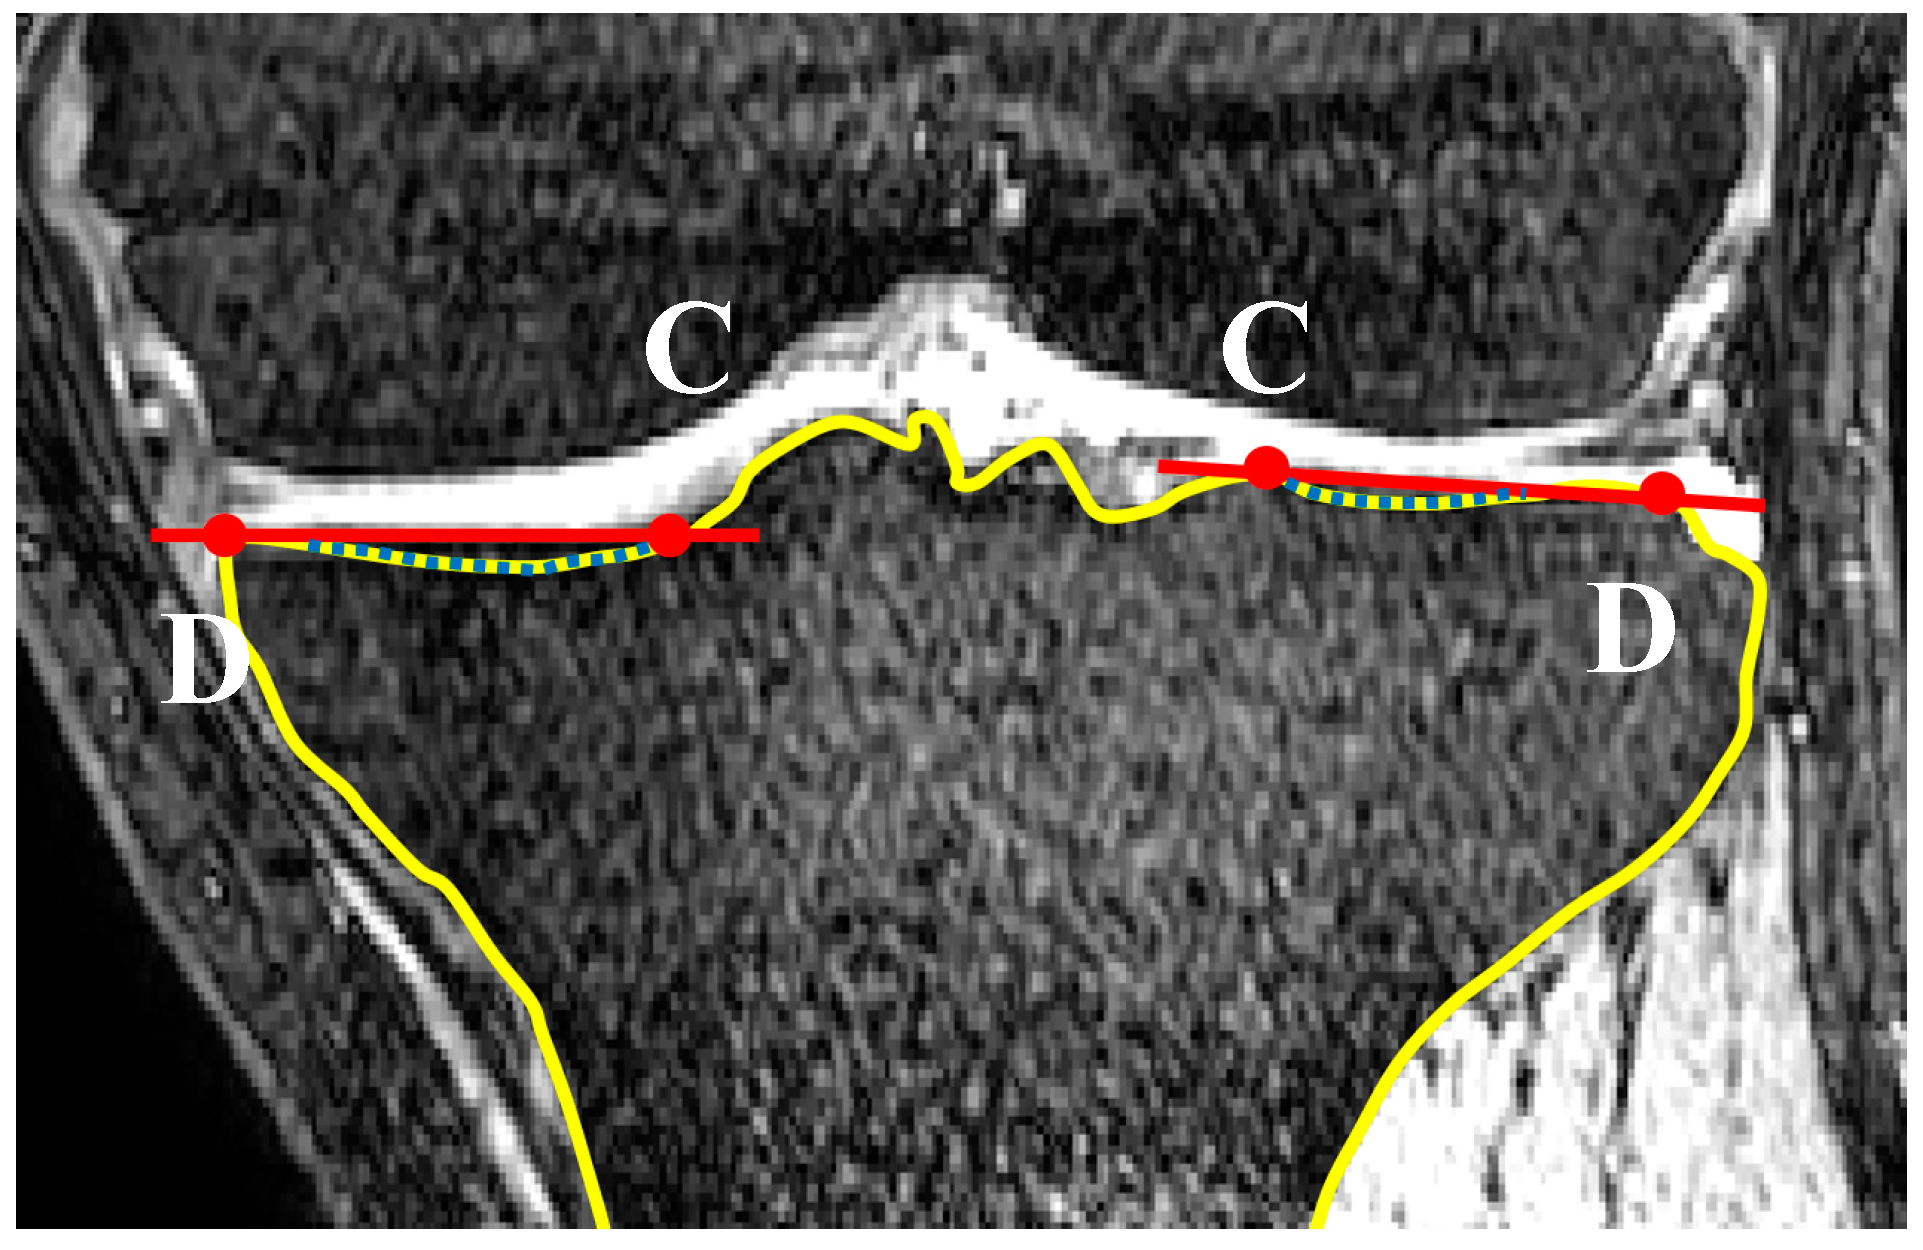

2.2. Coronal Tibial Slope Measurement Method

2.3. Concavity Zone